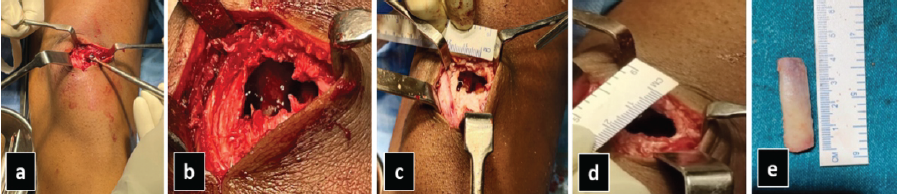

The patient underwent intralesional curettage with en bloc tumor resection. The resultant defect was filled using a tricortical iliac crest bone graft harvested from the ipsilateral ilium, and was shaped to fit the excised cavity (Fig. 2).

Figure 2: Intraoperative photographs demonstrating (a) intralesional curettage, (b) cavity following tumor removal, (c) transverse and (d) longitudinal measurements of the defect, and (e) dimensions of the harvested iliac crest bone graft.